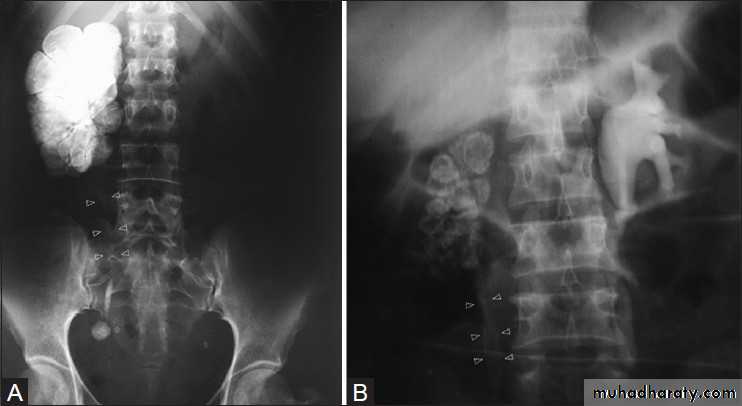

Congenital intrinsic pelviureteric junction (PUJ) obstruction

In this disorder, peristalsis is not transmitted across the pelviureteric junction.Childern and young adult

Dilatation of the pelvis and calices, with an abrupt change in caliber at the pelviureteric junction

the ureter is either narrow or normal in size.